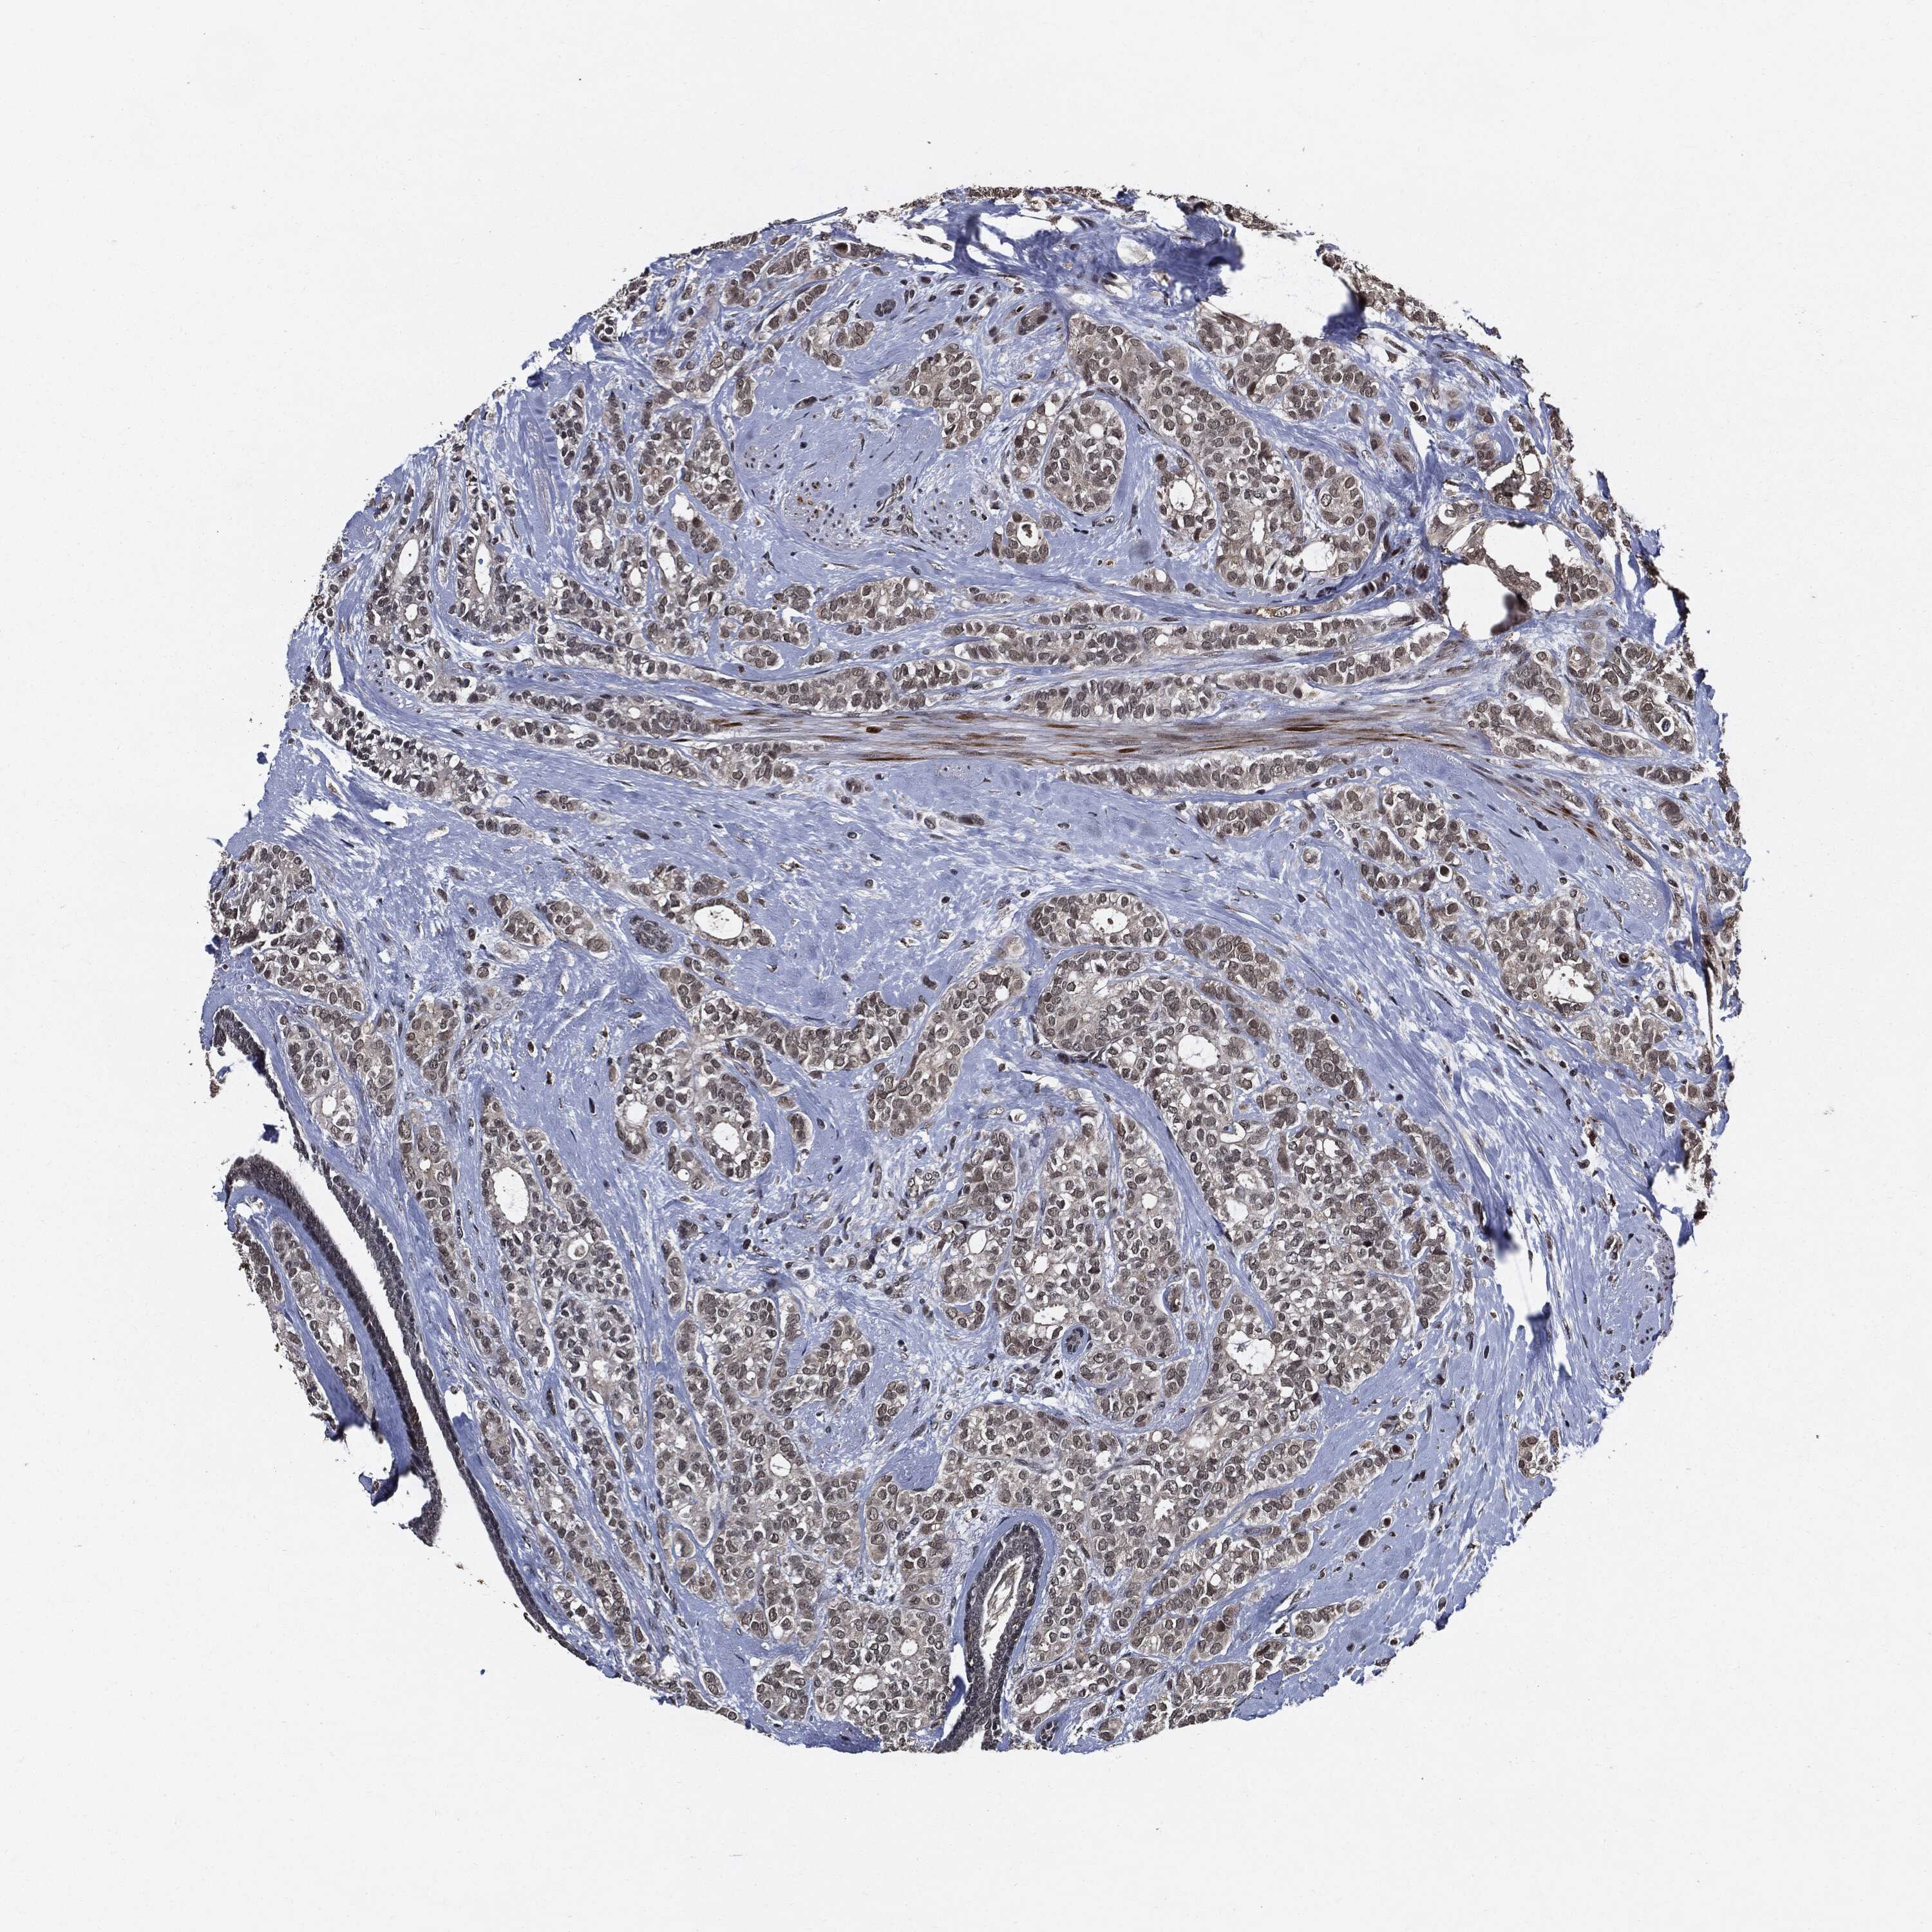

BRCA TCGA BRCA VALIDATION PROTEIN EXPRESSION